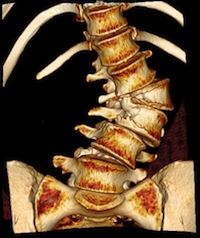

Traumatologie vertébrale - Fractures et Luxations

Fractures thoraciques et lombaires